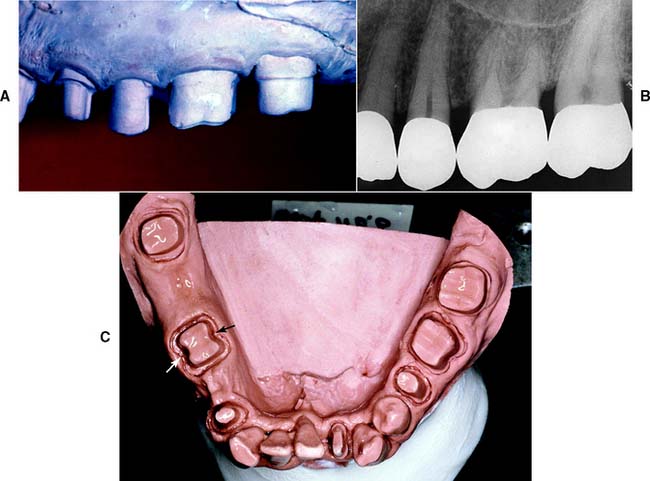

Fig. 7-15 A, Unhealthy gingival tissue resulting from overcontoured restorations. B, The tooth preparations are underreduced; C, Once the restorations are recontoured, gingival health returns.

Under most circumstances, a crown should duplicate the contours and profile of the original tooth (unless the restoration is needed to correct a malformed or malpositioned tooth). If an error is made, a slightly undercontoured flat restoration is better because it is easier to keep free of plaque; however, increasing proximal contour on anterior crowns to maintain the interproximal papilla25 (see Chapter 5) may be beneficial. Sufficient tooth structure must be removed to allow the development of correctly formed axial contours (Fig. 7-16), particularly in the interproximal and furcation areas of posterior teeth, where periodontal disease often progresses with serious consequences.

Fig. 7-16 A and B, Tooth preparations with adequate axial reduction allow the development of properly contoured embrasures. Tissue is conserved through the use of partial coverage and supragingival margins where possible. C, Preparing furcation areas adequately is important (arrows); otherwise, the restoration is excessively contoured, making plaque control difficult.